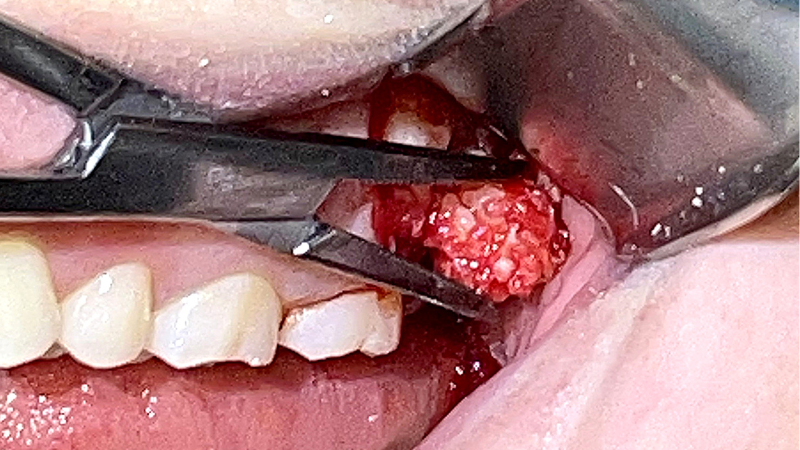

Zębiak złożony – opis przypadku

Title: Complex odontoma – a case report

Streszczenie: W artykule opisano przypadek pacjentki, u której podczas rutynowej diagnostyki radiologicznej wykryto zębiaka w okolicy zatrzymanego zęba 28.

Summary: The article describes a case of a patient in whom an odontoma was detected in the area of impacted tooth 28 during routine radiological diagnostics.

Zębiaki (ang. odontomas) stanowią najczęściej występującą grupę guzów zębopochodnych i według różnych autorów odpowiadają za 20-67% wszystkich tego rodzaju zmian (1, 2). W ujęciu histopatologicznym klasyfikuje się je jako łagodne nowotwory zębopochodne, jednak większość badaczy podkreśla, że w istocie mają one charakter malformacji rozwojowych o typie hamartoma, powstających na skutek zaburzeń w procesach odontogenezy (3, 4). W klasyfikacji Światowej Organizacji Zdrowia podkreśla się, że są to guzy mieszane, zawierające komponentę nabłonkową i mezenchymalną, z tendencją do formowania tkanek twardych zęba, takich jak szkliwo, zębina czy cement (5). Podział kliniczno-patologiczny wyróżnia dwa podstawowe typy tych zmian: zębiak zestawny (ang. compound [...]